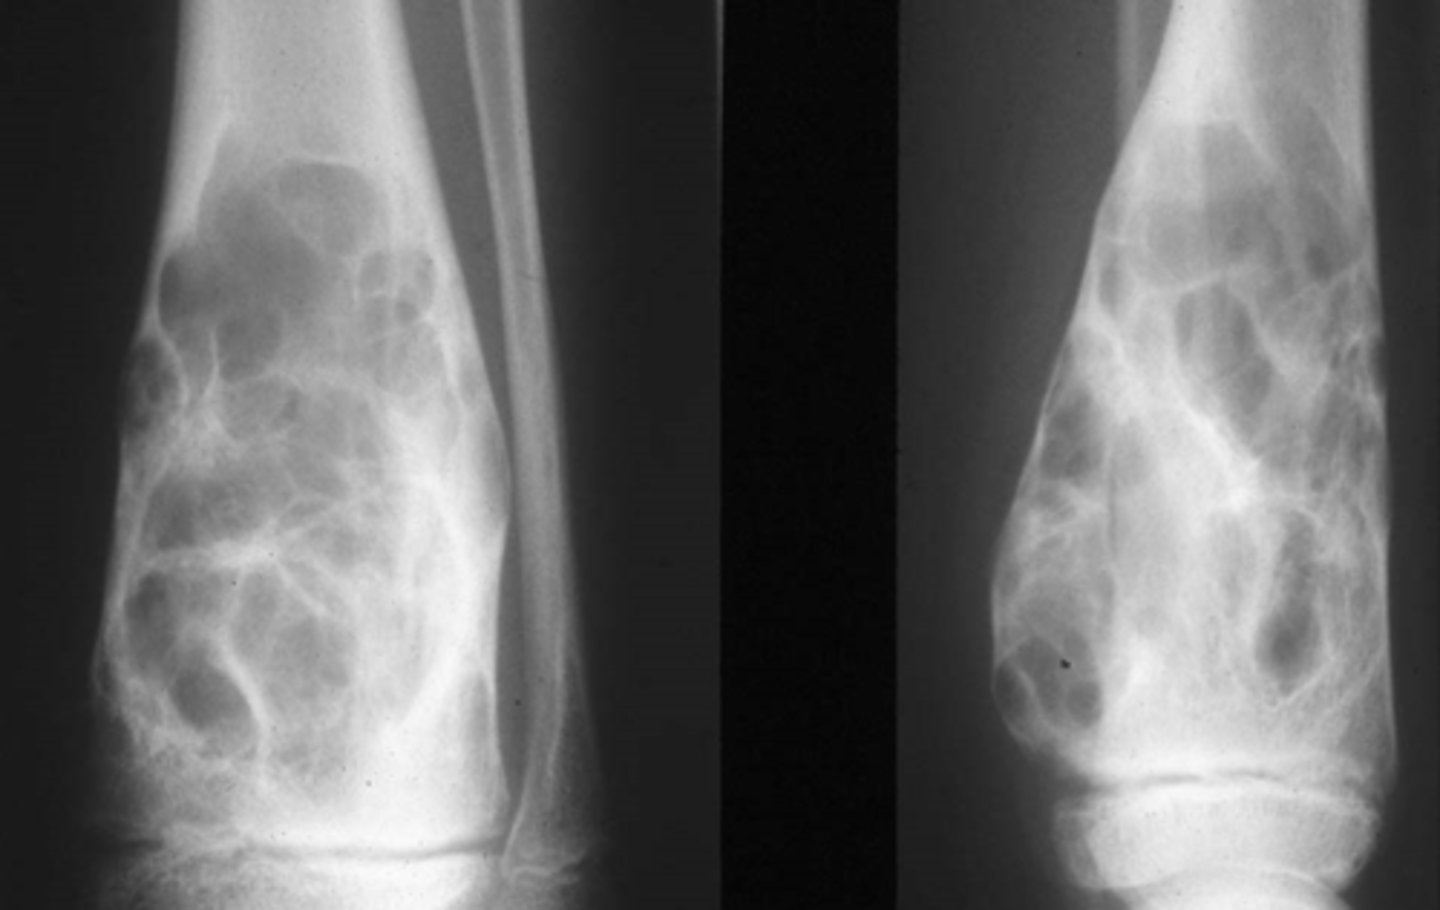

Vignette # 10

Chief Complaint: Mechanic presents with loss of grip strength. The patient reported having swollen fingers that previous hurt but the pain went away.

Objective Findings: ROM in his hands are decreased, notable swelling of the tissue in his fingers

Diagnostic imaging: X-ray

1. List the differential diagnoses. (Choose 3)

2. What else could be associated with this condition? (Choose 3)

3. What are the possible sequelae of this condition? (Choose 3)